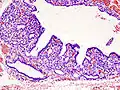

Hyperthyroidism is one of the most common endocrine conditions affecting older domesticated housecats. In the United States, up to 10% of cats over ten years old have hyperthyroidism.[63] The disease has become significantly more common since the first reports of feline hyperthyroidism in the 1970s. The most common cause of hyperthyroidism in cats is the presence of benign tumors called adenomas. 98% of cases are caused by the presence of an adenoma,[64] but the reason these cats develop such tumors continues to be studied.